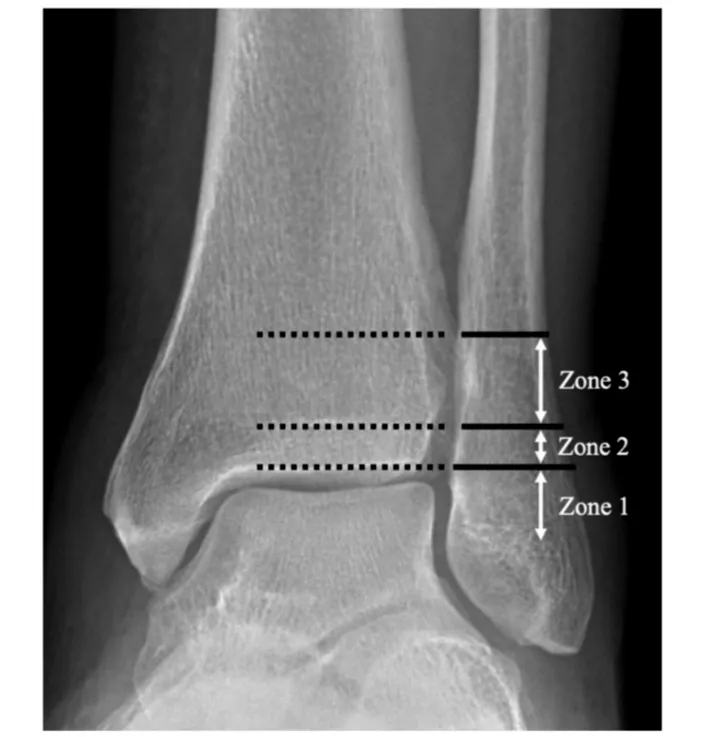

如何预测Danis-Weber B型踝关节骨折下胫腓联合损伤?

Lauge-Hansen分型与Danis-Webe分型为最常见的踝关节骨折分型,在对下胫腓韧带损伤的指导意义上,旋后外旋II°骨折通常认为合并下胫腓前韧带的损伤,下胫腓联合趋于稳定,可能无需下胫腓联合螺钉固定。而Danis-Weber B型骨折定义为骨折位于下胫腓联合水平,可能合并下胫腓联合损伤。